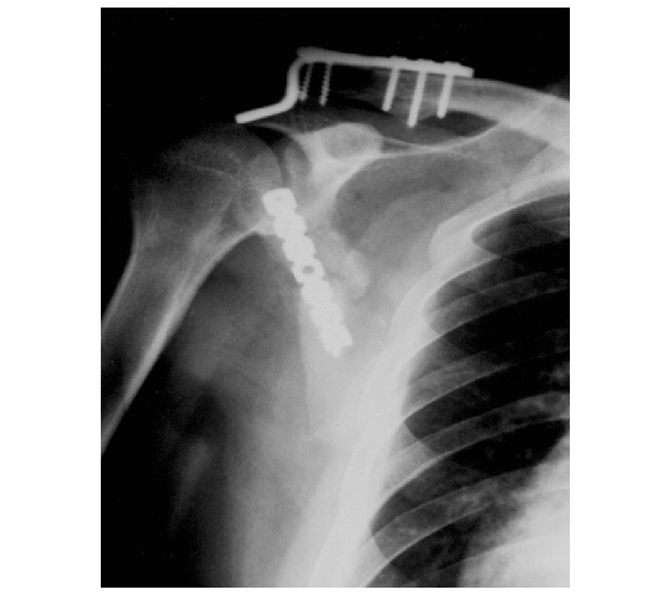

术后X线片可见,肩胛骨体部复位良好,因此,配合术后良好的患肢制动,缝线辅助固定技术同样可以稳定维持术中复位(图10)。

图10 采用缝线辅助固定后X线示骨折复位满意,内固定位置良好